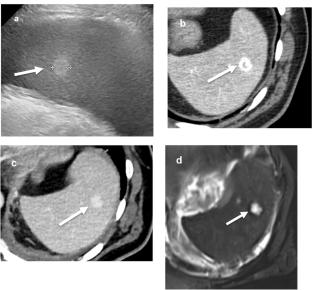

脾的横断面介入放射学(CSIR)在过去的二十年中得到了发展。当代数据显示,CT和us引导下的脾手术比以前认为的更安全,允许在临床适当时进行活检和引流。然而,在干预之前,需要对脾脏病变进行密切的影像学评估,以识别明确的良性,“不要触摸”病变以及可能需要活检的可疑特征。本文将首先关注脾病变的影像学检查和决策,然后讨论现代CSIR技术以最大限度地提高安全性和产出率。

Cross-sectional interventional radiology (CSIR) for the spleen has evolved over the past two decades. Contemporary data show that CT- and US-guided splenic procedures are safer than once assumed, allowing for biopsy and drainage when clinically appropriate. Prior to intervention, however, close imaging evaluation of splenic lesions is required in order to recognize definitively benign, “do not touch” lesions as well as suspicious features that might warrant biopsy. This manuscript will first focus on imaging workup and decision-making for splenic lesions, and then discuss modern CSIR techniques to maximize both safety and yield.